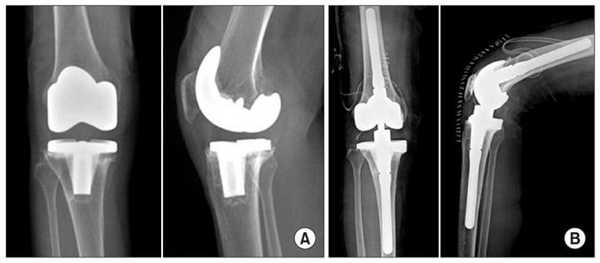

Две техники операции у одного пациента.

Одномыщелковая замена сустава на рентгене.

Сравнение двух типов операций.